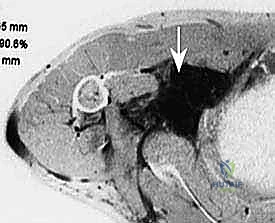

- التصوير بالرنين المغناطيسي (MRI) بالصبغة: وهو الفحص الذهبي. يوضح بدقة متناهية حدود الورم، ونوعه، ومدى التصاقه بالأعصاب والأوعية الدموية.

شاب يبلغ من العمر 28 عاماً، راجع العيادة وهو يعاني من ألم لا يُحتمل وضعف شديد في ذراعه اليمنى، مع عدم قدرة على تحريك أصابعه. أظهر الرنين المغناطيسي وجود ورم عصبي ضخم (Schwannoma) ملتف بالكامل حول الضفيرة العضدية في الإبط.

بفضل الله ثم بمهارة الدكتور هطيف في الجراحة الميكروسكوبية، تم فصل الورم عن كل شعيرة عصبية بدقة استغرقت 6 ساعات. النتيجة؟ استيقظ المريض بدون ألم، واستعاد حركة يده بالكامل خلال أسابيع، وعاد لعمله كمهندس بشكل طبيعي.